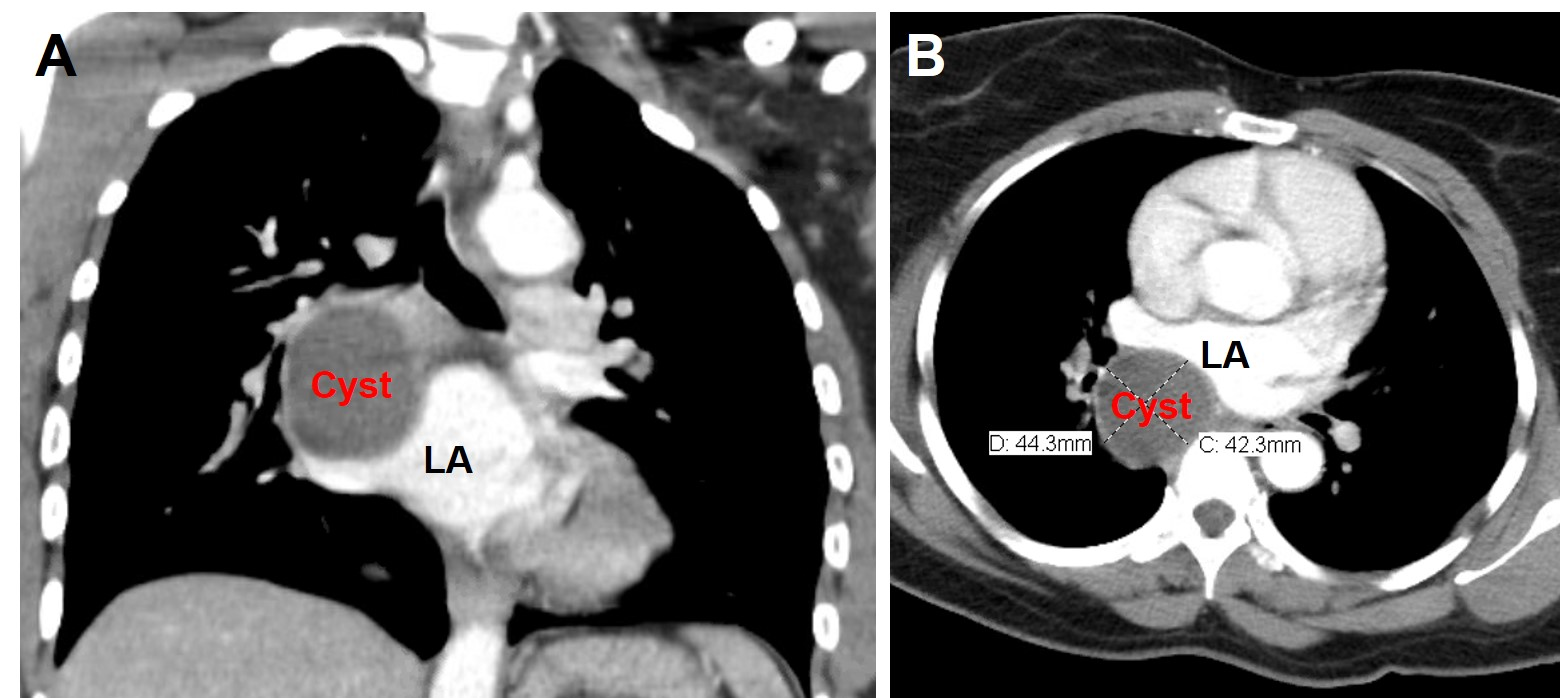

A 43-year-old African American female presented with progressively worsening chronic nonproductive cough, shortness of breath and palpitation without chest pain, lightheadedness or syncopal episodes. She was recently diagnosed with new-onset paroxysmal atrial fibrillation (AF) three month prior to presentation and was prescribed Eliquis for thrombosis prophylaxis. On presentation, an ECG revealed atrial fibrillation with RVR with a rate of 150bpm and prolonged QT interval. A Chest CT scan demonstrated a large 43x44x50 mmposterior mediastinal cystic lesion in the right infrahilar region causing a mass effect on the bronchus intermedius as well as the left atrium. The appearance of the mass on CT was consistent with abronchogenic cyst (Figure 1). The patient’s new-onset AF was attributed to the compression of left atrium and pulmonary vein. Patient was prescribed flecanide and subsequently pharmacologically converted to sinus rhythm.

Figure 1 Chest CT images showing large homogeneous, low-density, unilocular, well circumscribed mass 43mmx44mmx50mm (17 to 20 Hounsfield units), with direct extrinsic compression of the left atrium. (A) coronal and (B) axial views.